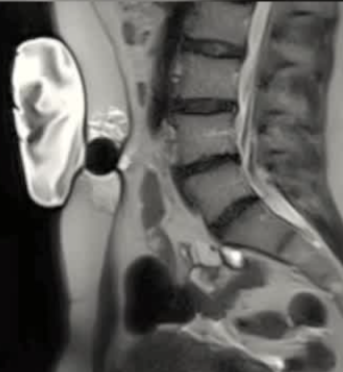

| 腹壁下病变 | MRI引导下 冷冻消融。装有热水的手套在皮肤表面保护皮肤 |

保护措施:几乎所有干预都需要辅助保护措施,其中水分离术(13/16,81.3%)和水分离术与温盐水填充手套的皮肤保护结合(9/16,56.3%)是最常见的保护措施。

采用冷冻循环(功率与持续时间)

| 12个月后随访 |

随访 早期:咨询 + CE-MRI

中期:咨询 +/- CE-MRI